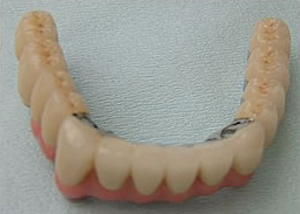

17.下の仕上がり上部構造3ケに分かれているが、入ると一体化します。

18.3ケのパーツが一体になりました。

19.下は作った最終本物の歯が入りました。

これで治療終了。